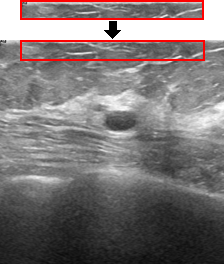

Loss Function. Ablation study results on the effect of MSE loss function are reported in Tab. 4 (second row) and Fig. 7. Although using an MSE loss does not necessarily lead to better quantitative metrics, Fig. 7 shows that it attempts to mitigate artifacts and retain the semantic integrity of the ultrasound image. Specifically, the middle image (without MSE) exhibits enhanced linear or streak-like artifacts, which may disrupt the homogeneity of tissue appearance (highlighted in the red rectangular region) and obscure finer structural details in the ultrasound image. Incorporating the MSE loss helps to reduce intensity fluctuations, creating a smoother and more consistent appearance, particularly beneficial in areas with subtle tissue boundaries.